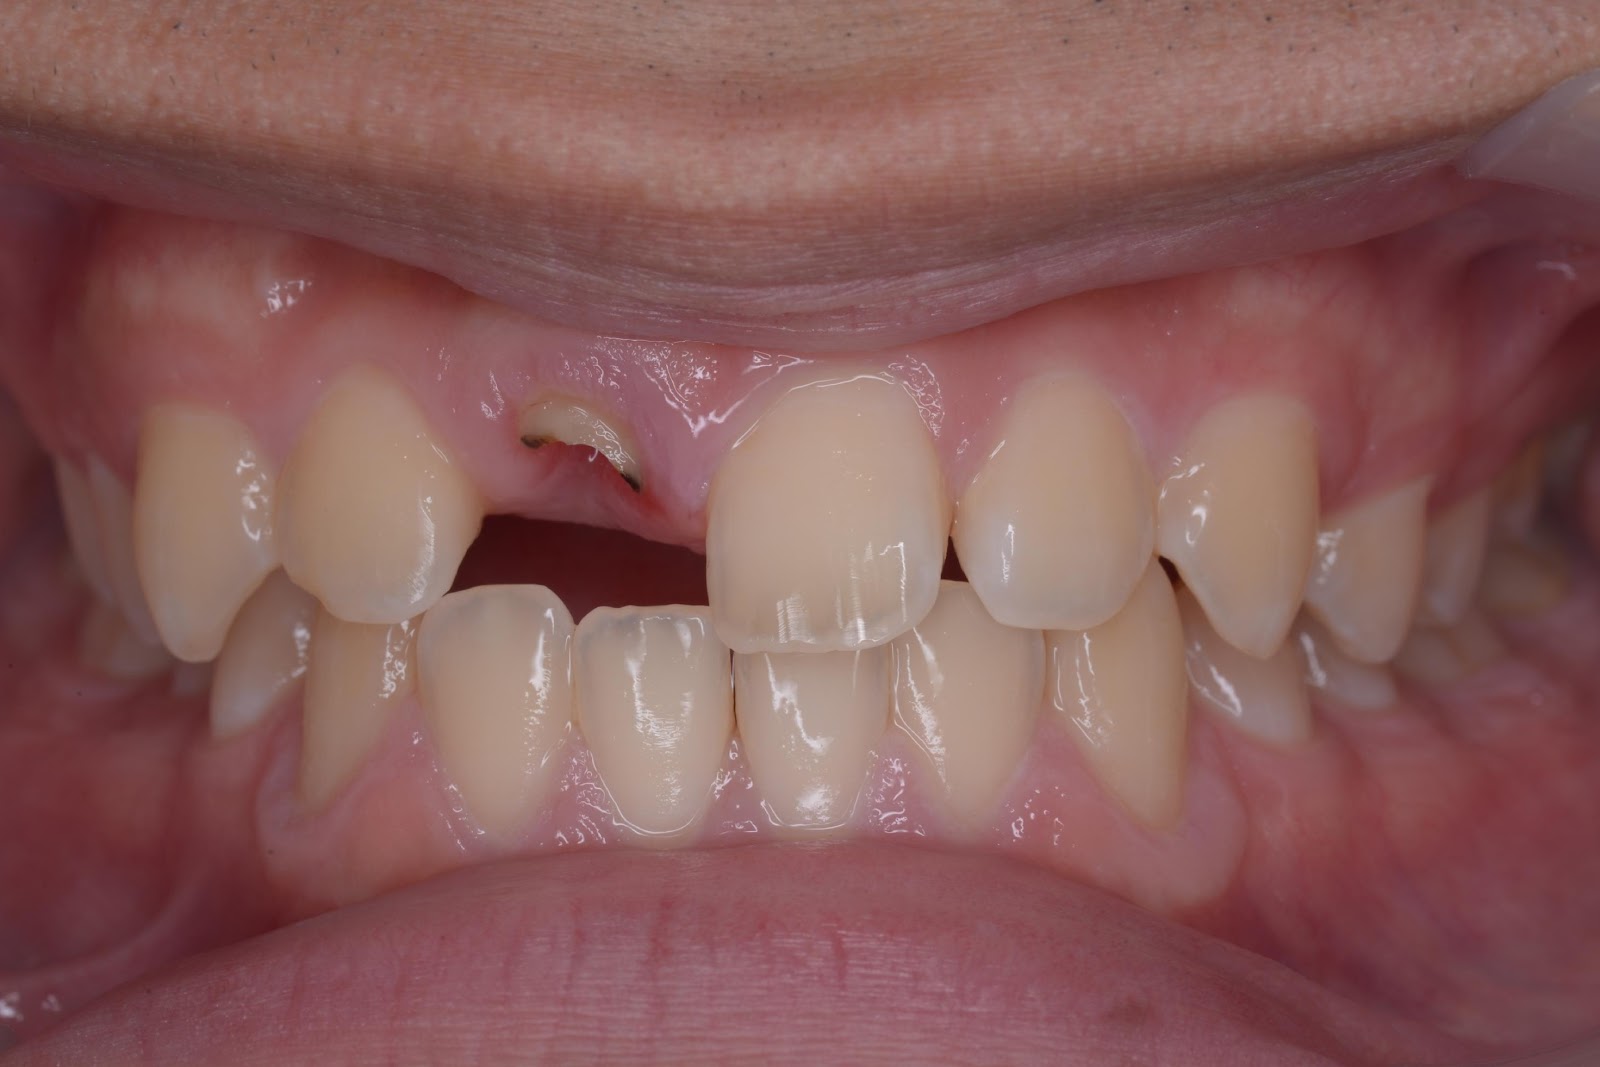

初診時

上部構造セット後

手術後

子供の頃に治療した前歯の差し歯が取れてしまった

来院時の状況と治療の経緯

歯の根だけが残っている状態なうえ、上あご側の歯質が非常に少なく、さらに歯茎に埋もれてしまっている状況だったため、差し歯での再治療は難しいと判断しました。

抜歯後はブリッジかインプラント治療を行う必要がある旨をご説明し、ご本人のご希望でインプラントを行うことになりました。 - 3

・抜歯

・インプラント埋入 1本

※前歯のため、抜歯とインプラント手術を行ったその日のうちに仮歯のセットまで行いました。 - 4